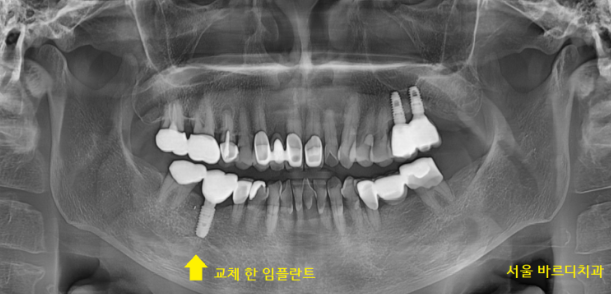

수술 후 4개월이 지나

보철을 새로 만드는 작업을 진행했습니다.

231130

임플란트 염증으로 교체를 한 치아이기에

더욱더 관리가 중요한데요.

관리가 안되면 똑같은 문제가 또 생길 수 있습니다.